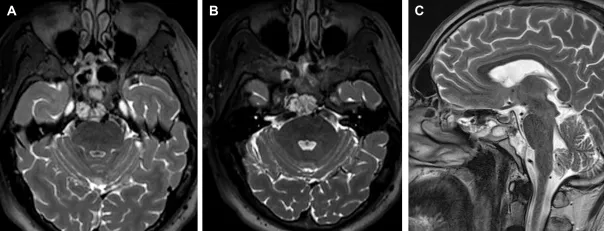

一名48岁的女性因右侧第六神经麻痹前来就诊。MRI显示一个大型斜坡脊索瘤,延伸至颞骨岩部、海绵窦、关节突和颈静脉孔、蝶筛隐窝以及咽后空间,疑似有硬脊膜内成分。

术后MRI确认了肿瘤的完全切除。在2个月的随访中,内镜检查未发现结痂,患者也未抱怨有任何鼻部不适。